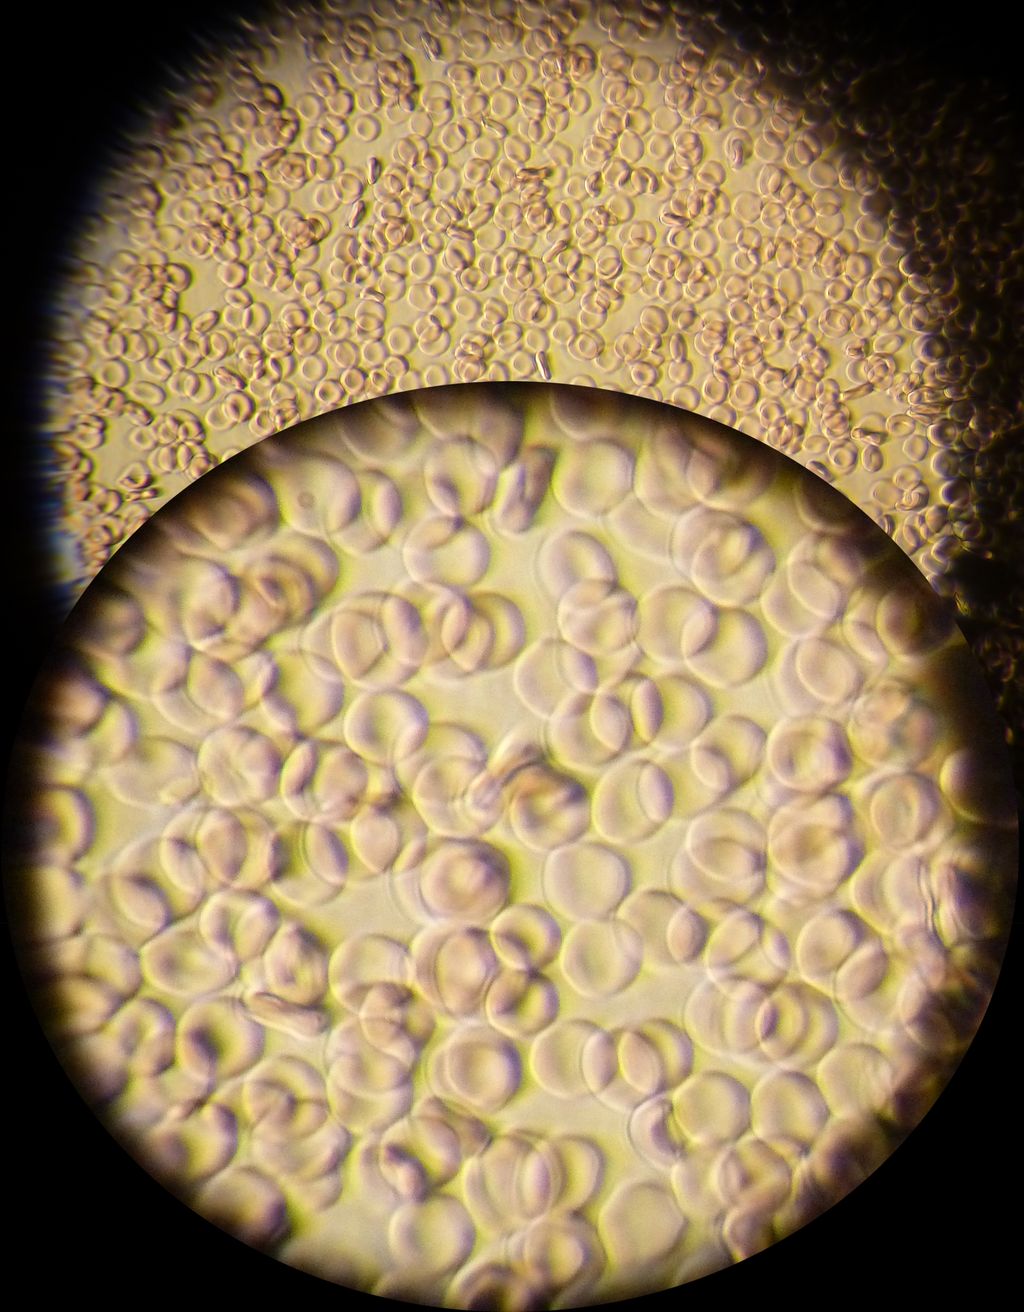

Se på preparatet under mikroskop med lav forstørrelse. Øk deretter forstørrelsen når du har fått et skarpt bilde. Ta gjerne bilder med mobiltelefonen gjennom okularet.

- Hva ser du?

- Kan du se forskjellen på røde og hvite blodceller?

- Hvilken form har de røde blodcellene?